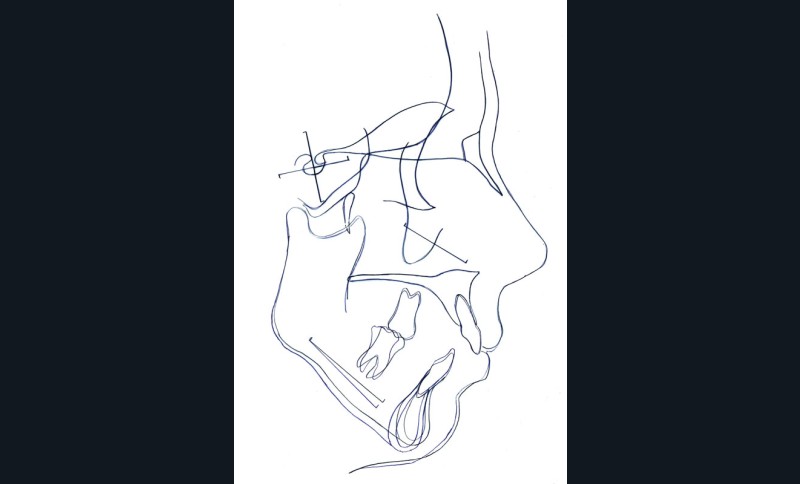

Étapes de traitement

(fig. 2, 3, 4, 5 et 6)

Le plan de traitement retenu a été le suivant :

– disjonction maxillaire assistée chirurgicalement

– préparation orthodontique avec recul molaire mandibulaire sur miniplaques à l’aide de corticotomies alvéolaires

– chirurgie d’avancée mandibulaire et génioplastie soustractive verticale

– finitions orthodontiques et éducation fonctionnelle active labio-linguale

– contentions collées maxillaire et mandibulaire

– suivi, en particulier de la fonction linguale